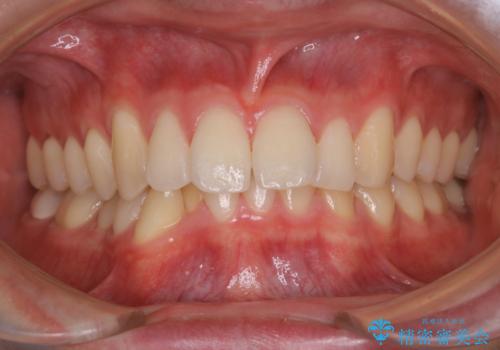

すきっ歯のワイヤー矯正による治療

- 前歯の隙間を閉じたいとのことで来院されました。

ワイヤー矯正にてスペースを閉じで、上下の歯のかみ合わせを改善することとなりました。

矯正治療には多少の痛みが伴いましたが、隙間もなくきれいな歯並びへと改善されました。